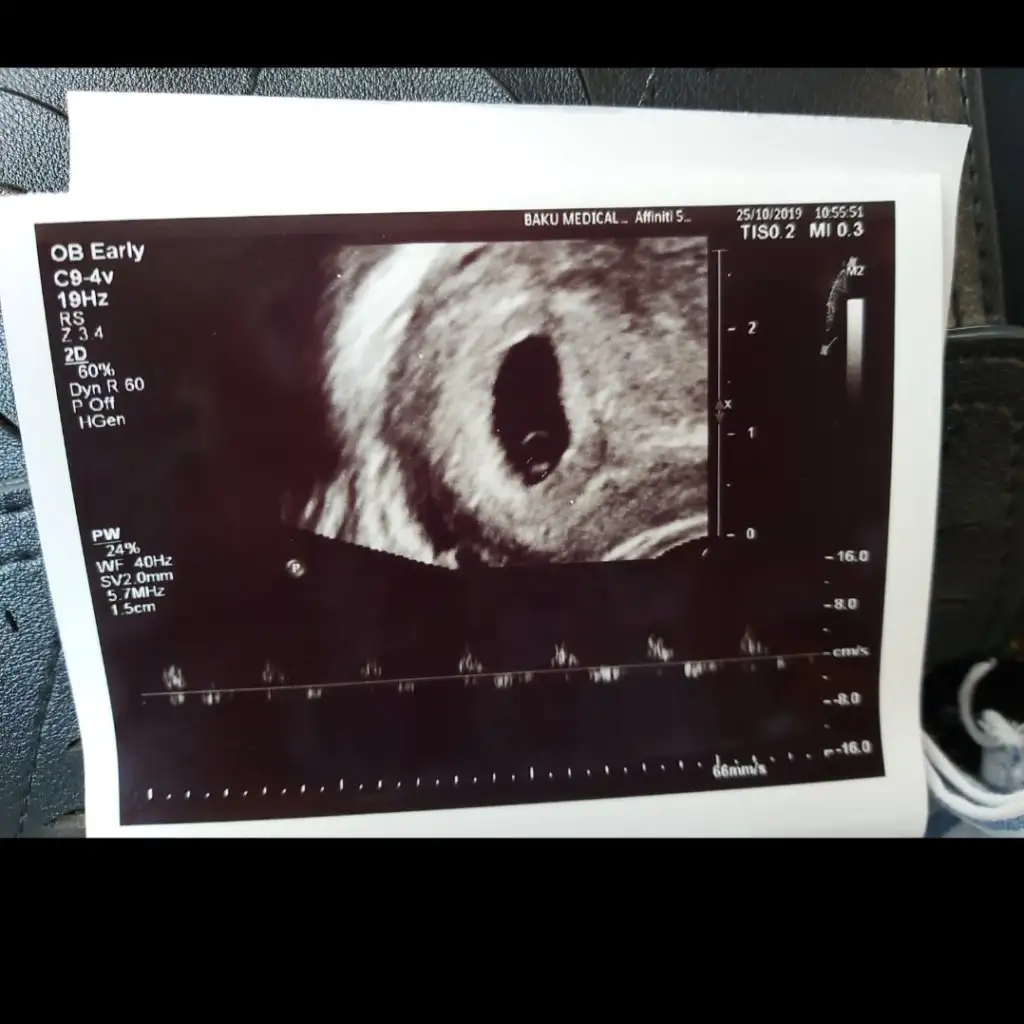

Kız teoriye görekızlaar lütfen bakın çok heyecanlıyım vajinal ultrasonla bakıldı 6 haftalık sol üstteki şey bebek ramzi teorisine göre nedir cinsiyeti

ayyy teşekkür ederim :)Kız teoriye göre

Tutmayan cok bu teoride onu da söyleyim gönlünüzdeki nasip olur inşallahayyy teşekkür ederim :)

kız da olsa erkekte olsa çok mutluyuz :) ama merak işteTutmayan cok bu teoride onu da söyleyim gönlünüzdeki nasip olur inşallah